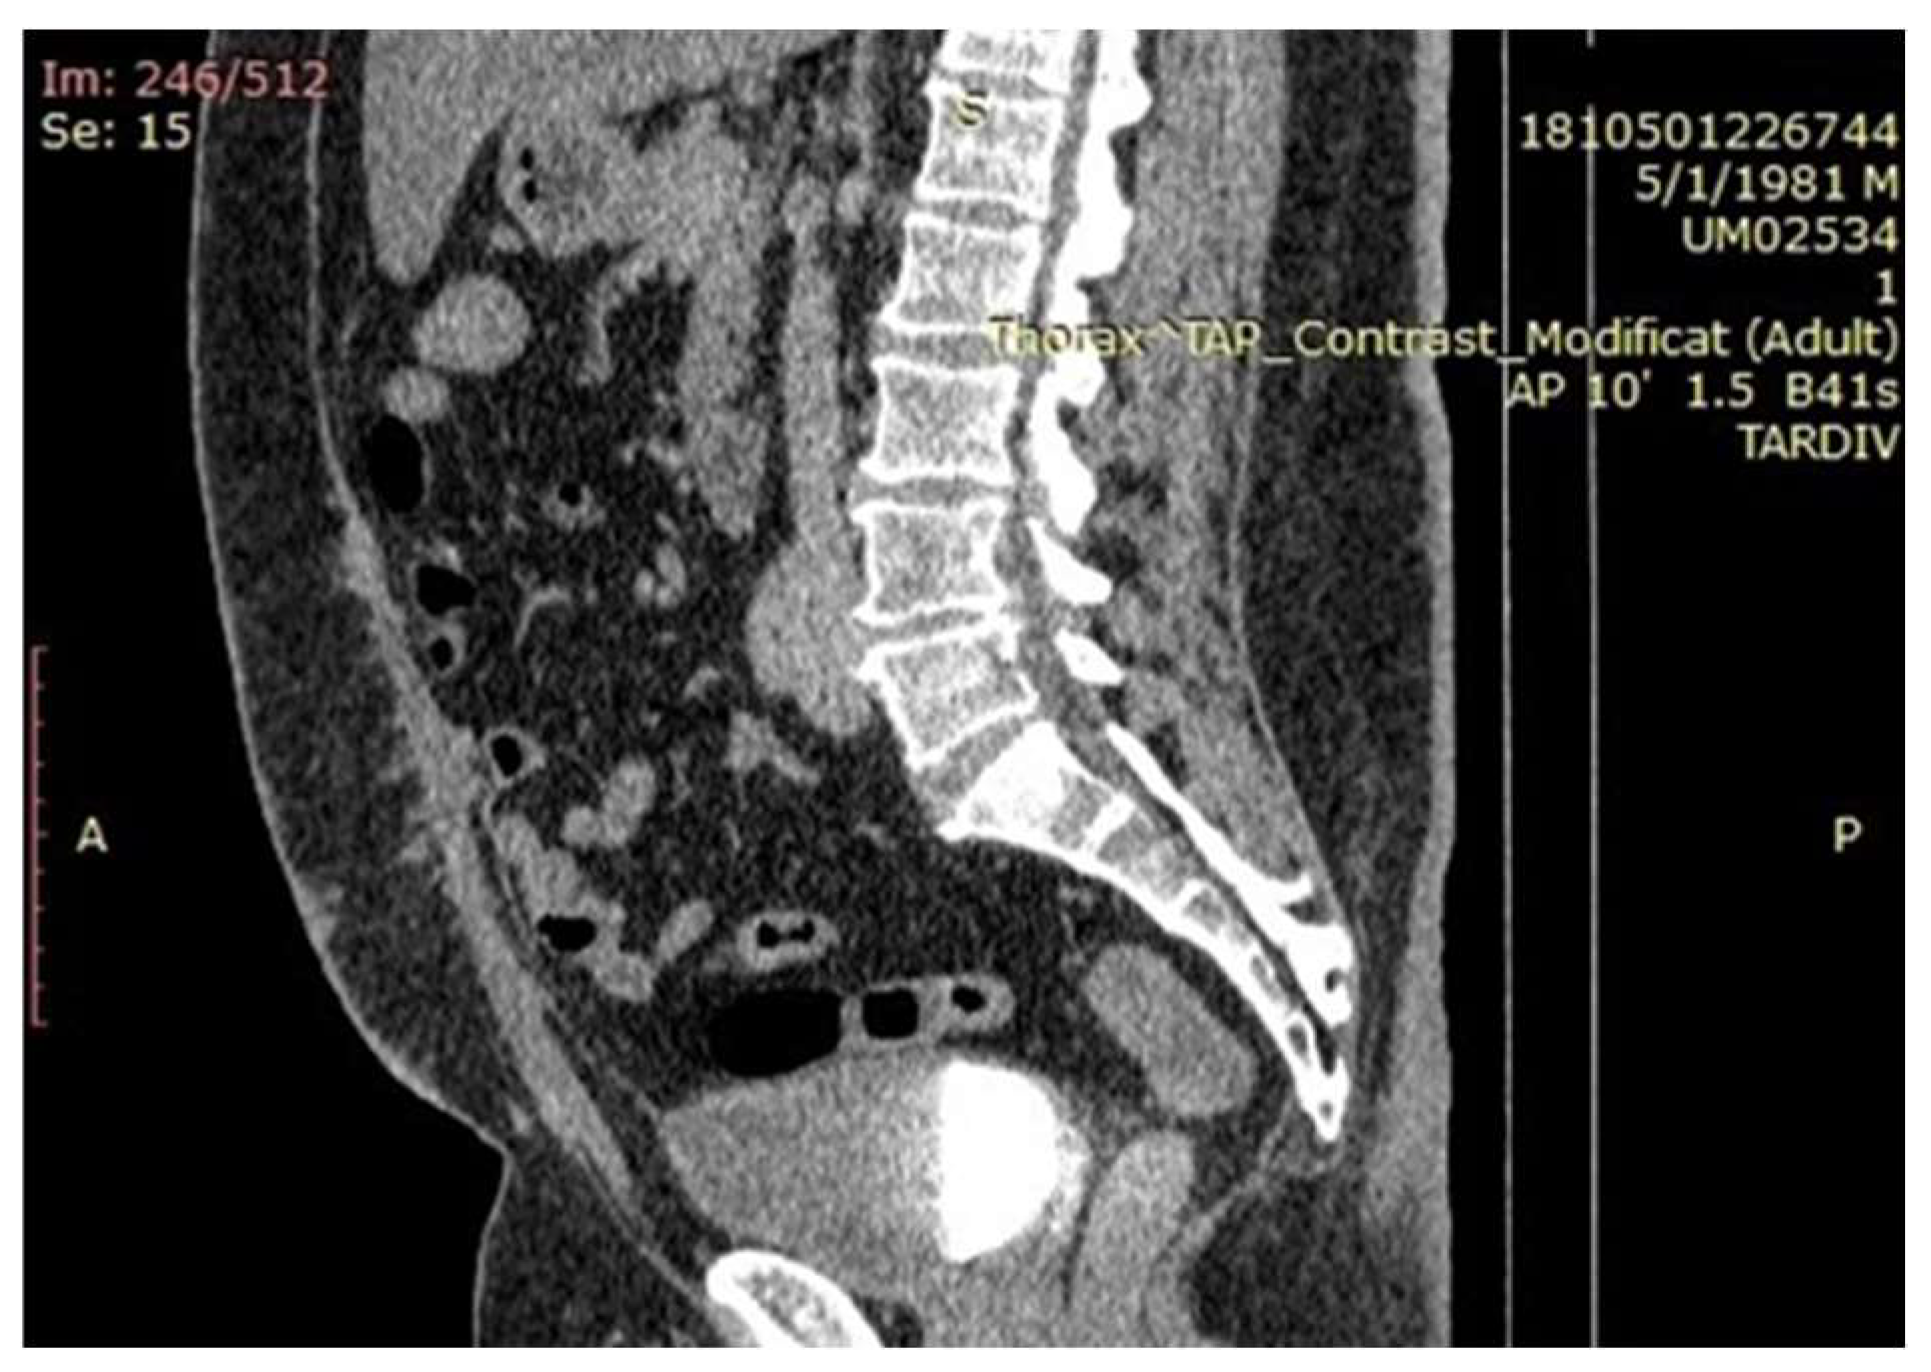

2.2. Imaging Findings